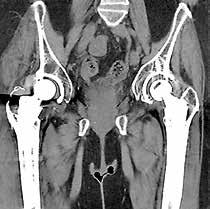

Metallartefaktreduktion serienmäßig

Mit SEMAR, der iterativen Metallartefaktreduzierung, können sogar schwierige Untersuchungen, z. B. mit Zahnfüllungen, Wirbelsäulenimplantaten, beidseitigen Hüftimplantaten, NeuroCoils und Schrittmachern durch einen flexiblen und reibungslosen Arbeitsablauf sicher ausgewertet werden. Der Single­Energy­Metall­Artefakt­Reduktionsalgorithmus beinhaltet zwei erfolgreiche Ansätze zur Reduzierung von Metallartefakten: Er kombiniert eine Strahlaufhärtungskorrektur mit dem Iterations­Hybridverfahren AIDR 3D Enhanced, um die Rauschtextur und scharfe Details neben Metallen wiederherzustellen. Dieser Prozess wird Schicht für Schicht über den gesamten Untersuchungsbereich durchgeführt, was in kürzester Zeit zu einem Artefaktfreien diagnostischen Bildstapel führt. SEMAR kann sowohl in schon hinterlegten, standardisierten Protokollen genutzt oder alternativ im Postprocessing über die Rohdaten ausgewählt und angewendet werden.

Die SEMAR-Metallartefaktreduktion minimiert die durch Implantate verursachten Bildstörungen und sichert so die Diagnostik sowohl des Metalls selbst wie auch des umliegenden Gewebes.